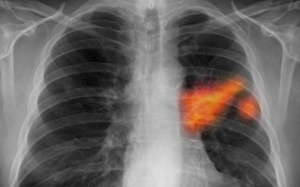

Có rất nhiều loại ung thư, mỗi bệnh biểu hiện khác nhau. Nhiều trường hợp mắc bệnh nhưng không có biểu hiện hoặc chỉ phát ra ở giai đoạn cuối. Dưới đây là 10 dấu hiệu cảnh báo...

Người ta thường nói ung thư di căn đồng nghĩa với cái chết đang đến gần và cơ chế di căn của các tế bào ung thư đã được các nhà khoa học Mỹ tìm ra.